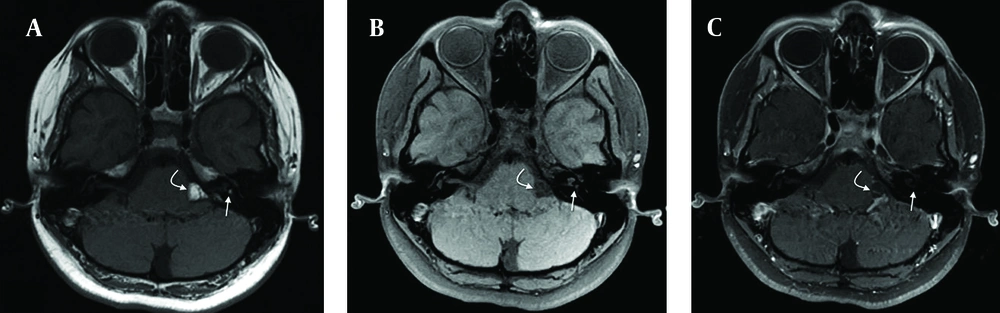

The patient was subjected to radiological examination and computed tomography revealed a homogeneously hypoattenuated CPA mass (Figure 1). MRI showed a hyperintense 15×7 mm sized left CPA mass that encased the left VIII cranial nerve on T1-weighted images. The mass signals were suppressed on fat saturated images. The eighth cranial nerve was followed up and a 4 mm diameter lesion with a similar radiologic feature in IAC was seen (Figures 2 and 3). After administration of contrast with fat suppression, axial T1-weighted image displayed suppression of the CPA and intravestibular mass, and no enhancement was observed (Figure 4). These findings together with the confirmation on fat suppressed images were highly suggestive of a lipoma. Our patient was followed up clinically and radiologically for two years and there has been no progression.

A) Axial T1-weighted image shows a hyperintense mass due to lipoma in the left cerebellopontine angle (curved white arrow) and left internal acoustic canal (straight white arrow). B) Axial T1-weighted image with fat saturation displays saturation of lipomas in the left cerebellopontine angle (curved white arrow) and left vestibule (straight white arrow). C) Enhanced axial fat saturation T1-weighted MR image shows no enhancement of lesions